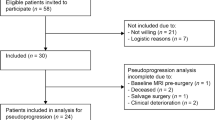

The UCLA Medical Center institutional review board approved this study (IRB IRB#15-000467). Patients from 2003 to 2016 with histology confirmed LGG (WHO II) who underwent at least two 18F-FDOPA PET scans and MRI scans within 3 months of the PET scans, and had no surgical intervention between scans were eligible for inclusion. A total of 27 patients were identified as having two or more 18F-FDOPA PET scans, MRI scans consisting of at least pre- and post-contrast T1-weighted images and either T2-weighted turbo spin echo or T2-weighted fluid-attenuated inversion recovery (FLAIR) images with sufficient quality, lack of contrast enhancement, and adequate clinical information including survival. When available, isocitrate dehydrogenase (IDH) 1 mutational status, 1p19q codeletion status, and O6-methylguanine–DNA methyltransferase (MGMT) promoter methylation results were obtained from the patient’s clinical chart. IDH mutation status was determined by genomic sequencing analysis using polymerase chain reaction (PCR) and/or through immunohistochemistry (IHC) of resected tumor tissue. 1p/19 co-deletion status was identified using fluorescence in situ hybridization (FISH) or Foundation medicine. MGMT methylation status was determined by PCR analysis. Malignant transformation was determined either by histology or radiological changes consistent with transformation (e.g. emergence of contrast enhancement suggestive of transformation to higher grade as indicated in the clinical radiology report). OS was measured from the time of the 2nd PET scan until death. Table 1 summarizes these patient demographics and molecular information.

A total of 27 patients met the inclusion criteria for the current study. The mean age for these patients was 50.9 ± 13.4 s.d. years and 29% were female. The average time interval between serial 18F-FDOPA PET exams was 1.3 years (range 125 days to 4.7 years) and matched MRI scans used in the current study was 1.3 years (range 125 days to 4.6 years). According to WHO 2007 histological criteria, 9 patients had low-grade diffuse astrocytomas (LA), 8 patients had low-grade oligodendrogliomas (LO), and 10 patients had low-grade mixed oligoastrocytomas (OA). A total of 15 patients were IDH mutant gliomas, 5 patients were IDH wild type, and 7 patients did not have known IDH status. Ten patients were 1p19q codeleted, 9 patients were non-codeleted, and 8 patients did not have known 1p19q status. A total of 9 patients were MGMT methylated, 7 were unmethylated, and the remaining 11 did not have MGMT status available. Approximately 48% of patients (13 of 27) were not on active therapy between the two PET and MRI exams and about 44% of patients (12 of 27) demonstrated histological or radiographic evidence of malignant transformation within 6 months of the 2nd MR-PET exam. Within 6 months of the 2nd PET scan, about 52% (14 of 27) patients accepted chemotherapy and/or radiation treatment. Of the patients who accepted therapy, about 43% (6 of 14) had malignant transformation.